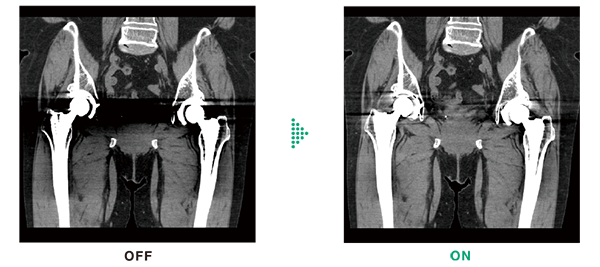

HiMAR Plus reduces metal artifacts using sequential approximation processing. It extracts metal parts,estimates artifacts, and then corrects them. The strength of the effect can be selected, allowing you to use it according to your purpose. HiMAR Plus can be used in combination with Intelli IPV.